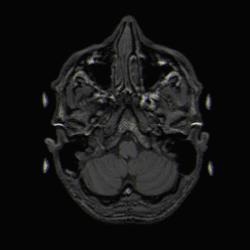

Os pacientes sofrem de uma variedade de sintomas característicos de uma lesão maciça focal ou multifocal. A RM geralmente mostra tumores com realce homogêneo de contraste dentro da substância branca periventricular profunda. Multifocalidade e realce não homogêneo são típicos para pacientes com sistema imunológico enfraquecido. A análise do linfoma do SNC é extremamente importante no diagnóstico diferencial das neoplasias cerebrais. Ressalta-se que a administração de corticosteróides pode levar ao desaparecimento completo do realce, dificultando o diagnóstico das lesões. Consequentemente, se o linfoma do SNC for considerado no diagnóstico diferencial, os corticosteróides devem ser evitados, a menos que o efeito de massa cause um problema sério e imediato no paciente.